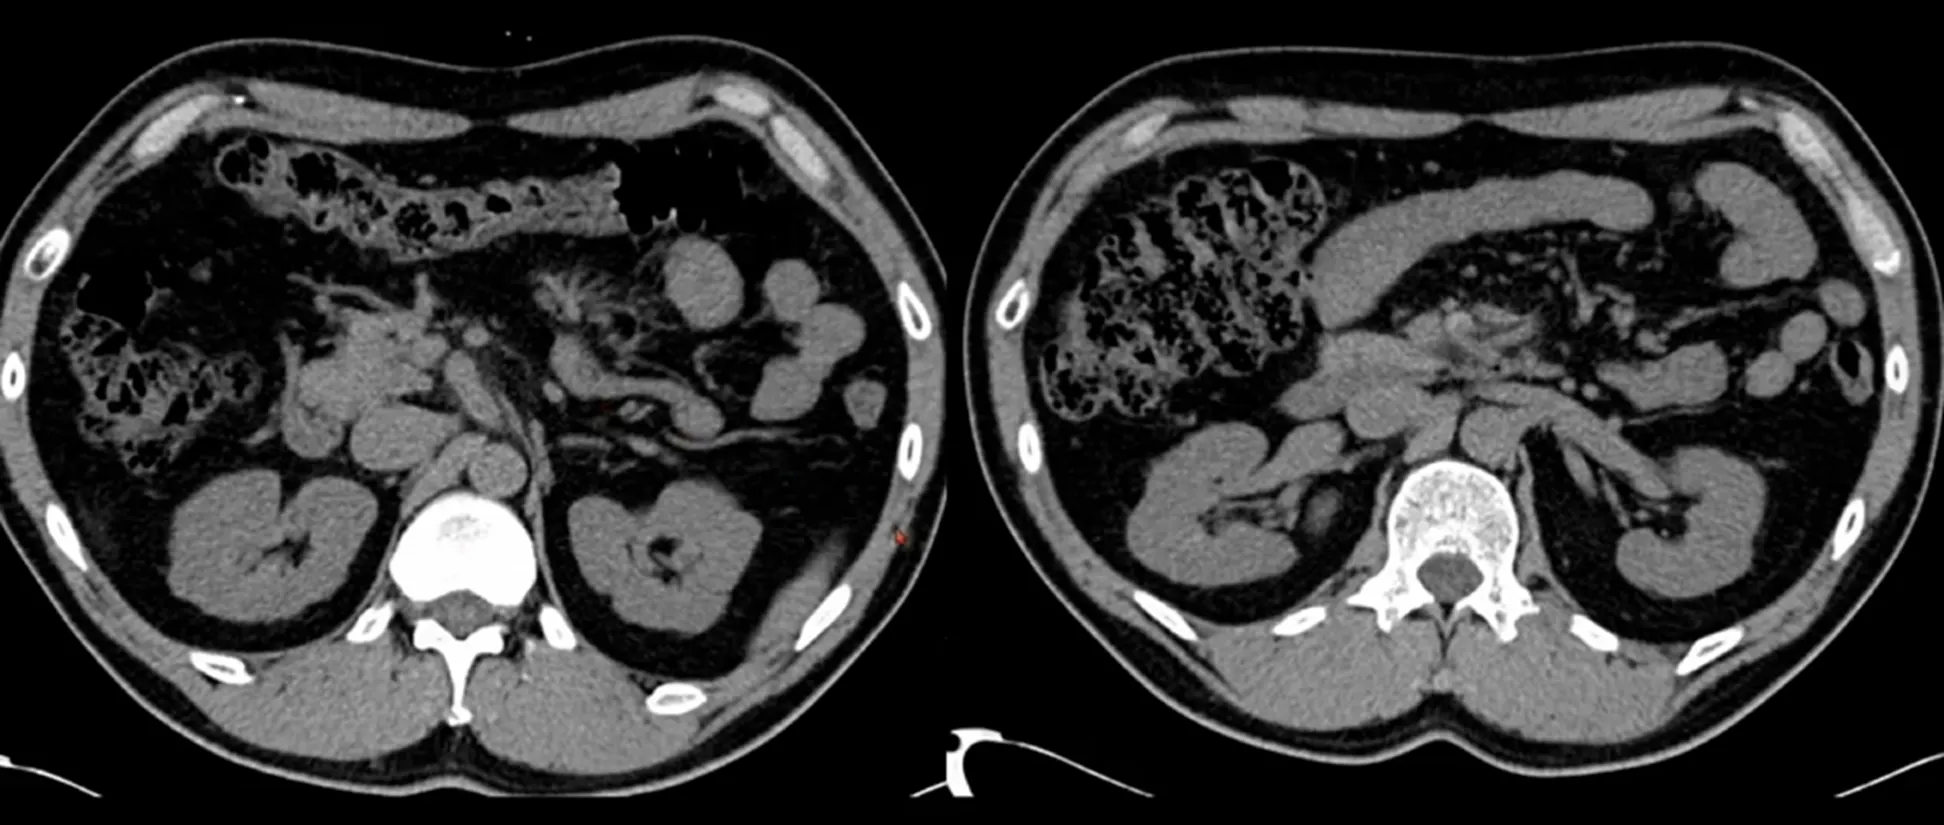

Case 5: Urinary tract infection

•

M/77

C/C: Lt. PCN remove site leakage, no self voiding

Hx : bladder cancer s/p Op with neobladder